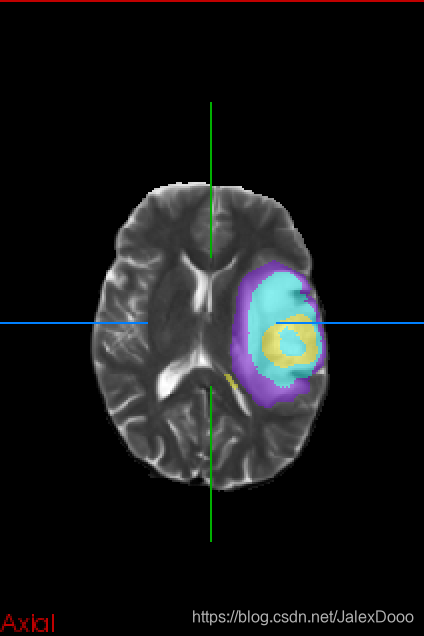

用在了大脑胶质瘤分割上,2D的处理方式,论文也是2D的处理形式,实在差劲;然后改成3D处理,还是差劲。

3D